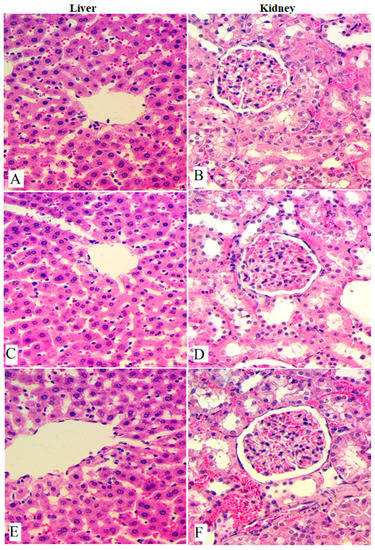

3.2. Acute Toxicity

3.3. In Vivo Anticancer Study